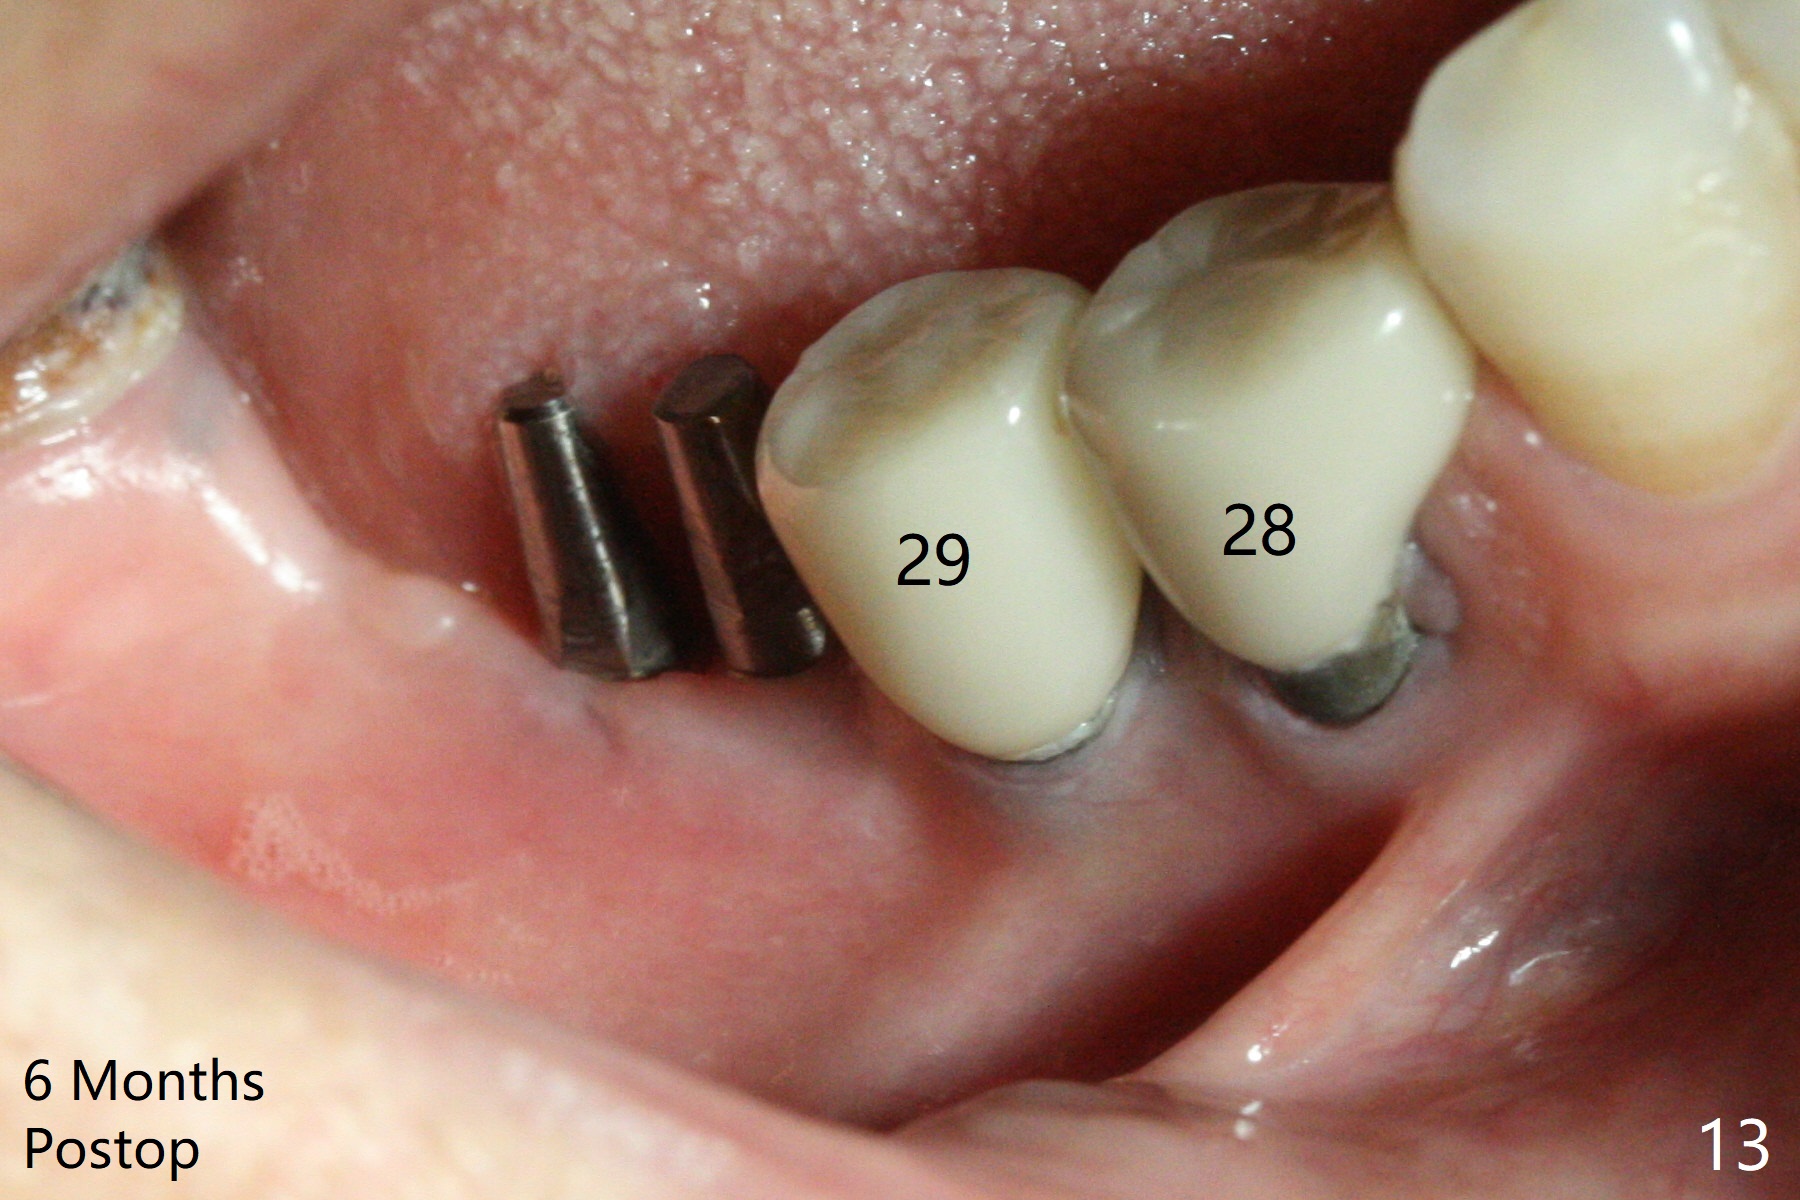

The edentulous ridge at #30 is narrow (Fig.1). After ridge reduction, osteotomy is initiated with 1.2 mm drill for 10 mm; the mesial osteotomy is to be changed (Fig.2 red line). Using a 1.2 mm drill placed in the distal osteotomy (Fig.3 D), the mesial osteotomy changes in trajectory with subsequent placement of a 2.5x10(4) mm 1-piece implant. Since the mesial implant is high in occlusion, the cuff of the distal implant is changed to be 2 mm (Fig.4 (shorter black line)). Panoramic X-ray is taken to show no violation of the Inferior Alveolar Canal (Fig.5 red dashed line). These two 1-piece implants are slightly lingually placed (Fig.6). The crestal bone around the implants resorbs without thread exposure 5 months postop (Fig.7). Impression is taken for a splinted crown (Fig.8-12). There is no metal show around the 2.5 mm 1-piece implants 6 months postop (advantage) vs. that at #28 and 29 (Fig.13). Bitewing is taken post cementation to determine whether residual cement is present (Fig.14). There is periodic swelling and pain in the lower right quadrant 2 years post cementation (Fig.15). In fact periimplantitis appears to have developed at #28 (Fig.16) with loss of the buccal bone (Fig.17,18). The buccal bone loss is less at #29 (Fig.19) and #20 (Fig.23) and no at #30 mesial and distal implants (Fig.20,21). A much smaller implant will be placed lingually at #28 immediate (Fig.24,25).